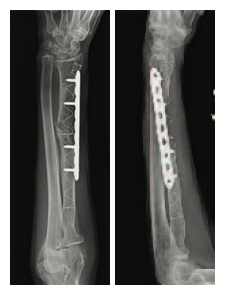

Diagnosis: Metastatic Renal Cell Carcinoma with pathologic fracture of the right radius and left ulna and significantly compromized bone quality.

Description of treatment: Radiation to lesion followed by surgery utilizing two IlluminOss implants sizes: 11 mm x 180 mm in the radius augmented with a 3.5 mm small fragment LCP plate and 11 mm x 220 mm in the ulna augmented with a 3.5 mm small fragment LCP plate. To insert each implant, a small incision was made and an awl inserted. This was followed by the use of a reamer to create a pathway for the implant to be inserted into the intramedullary canal. A strong, PET (Dacron) balloon catheter was inserted into the intramedullary canal and infused with a 3 part multi-functional, methacrylate, photodynamic liquid monomer. A light box emitting visible blue light (436 nm) hardened the implant on demand. The implants provided immediate strength and rotational stability. Dr. Williams chose to utilize plates in conjunction with the IlluminOss implants due to the patient’s significantly compromised bone quality. The implants created a stable construct enabling the plates to be secured which was not achievable with hardware alone in this severely deteriorating and fragile bone.

Right Radius

6 Week Post-op